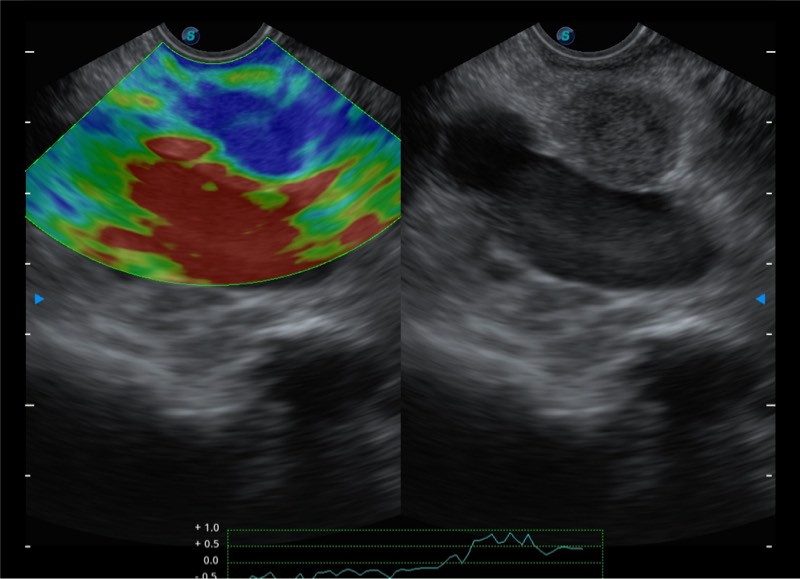

基于二十年的超声技术积累,亚星官网提供了最新一代的独立超声主机,在提供高质量图像的同时满足多学科使用。具备常见多普勒技术并提供弹性成像、声学造影等高端影像技术。新一代传感器具有更强的抗干扰能力并减少图像伪影。

4-12MHZ宽频输出